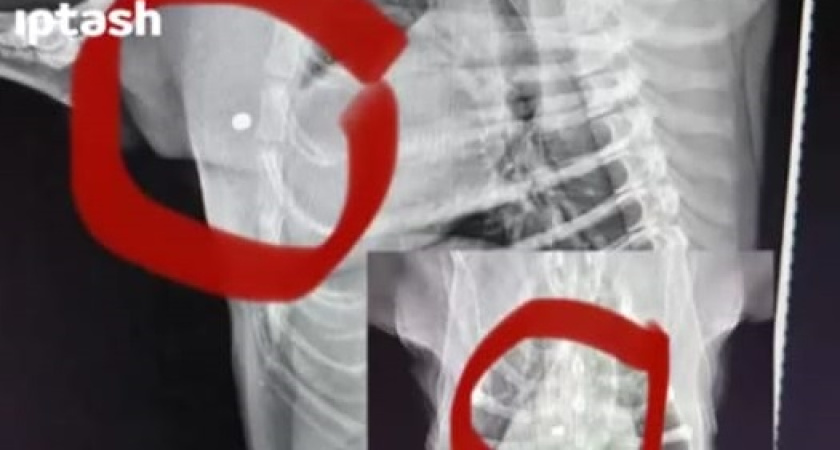

Мужчина обратился за помощью к полицейским. Свою собаку отвез в клинику. Сделали снимок – пули находятся близко к жизненно-важным органам. Вскоре проведут ветеринарную экспертизу.